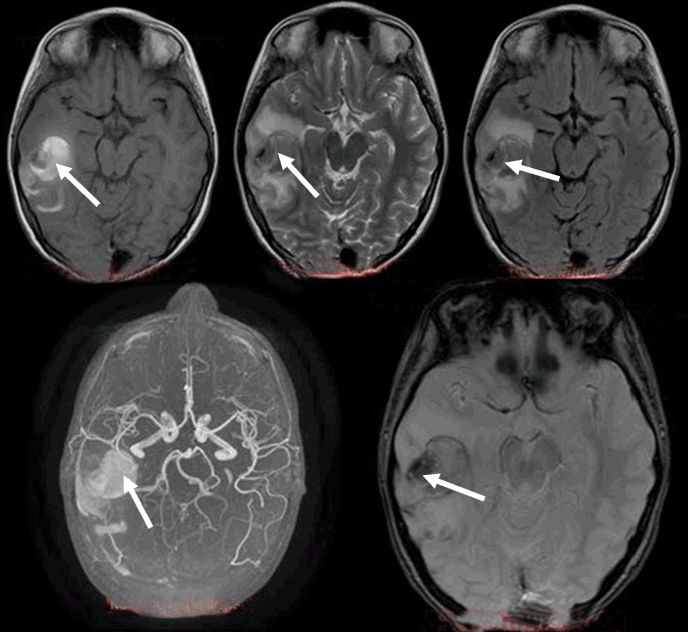

An electroencephalography (EEG) study detected focal cerebral disturbances. A repeat MRI scan (with contrast) and magnetic resonance angiography (MRA), indicated a hemorrhagic infarct in the territory in a subacute phase with related edema (hemorrhagic stroke). Magnetic resonance angiography further recognized stenosis of the right middle cerebral artery (MCA) with obstruction of the posterior peripheral branches (Figure 3).

Figure 3: Magnetic resonance imaging and magnetic resonance angiography scan after 10 days of the event (from above to below, T1W, T2W, FLAIR, MRA reconstruction and T2 GRE images). Arrows depict the evolution of signal changes.